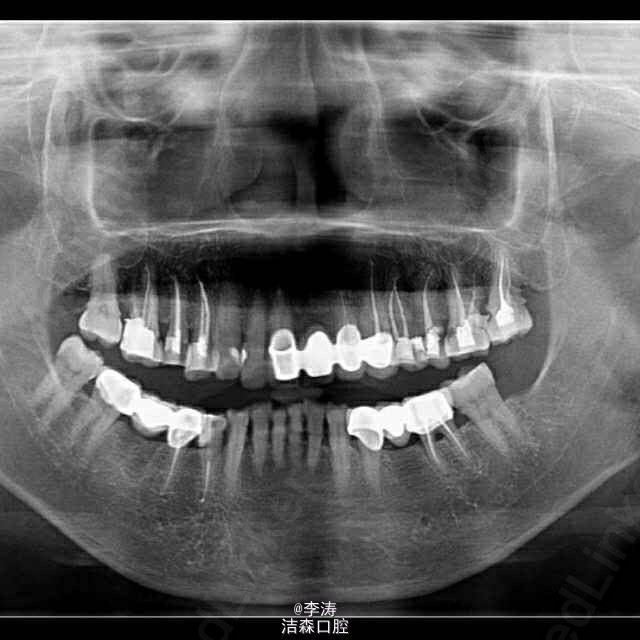

多颗牙牙痛根管治疗1例

这是接诊的最难的一例病例,患者65岁女性,主诉牙齿疼痛,检查基本上全口邻面深龋,治疗完左边,右边又痛,结果是全口多数牙都被根管治疗,治疗完准备不做冠,又被咬崩,结果又不得不将根管治疗的牙全做冠。